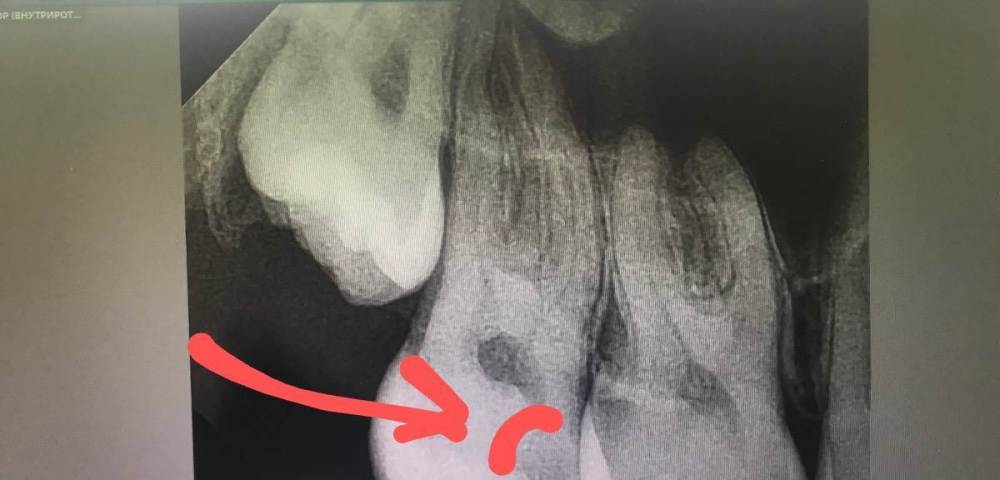

cryptiik Опубликовано 16 февраля, 2023 Поделиться Опубликовано 16 февраля, 2023 Расшифруйте, пожалуйста, снимки 16 и 17 зубов. Ссылка на комментарий

annda Опубликовано 16 февраля, 2023 Поделиться Опубликовано 16 февраля, 2023 Для точной оценки глубины и расположения полостей нужны прикусные снимки.А для диагноза -жалобы и объективные данные,а не вот эта абстракция. 1 Ссылка на комментарий